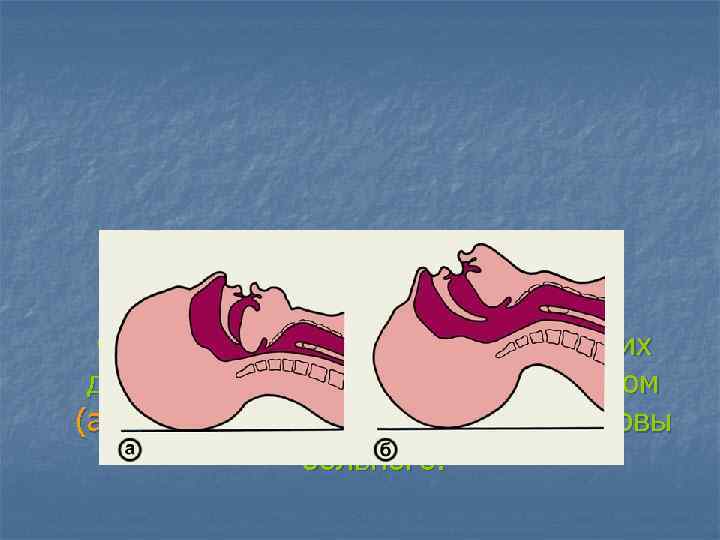

Схематическое изображение верхних дыхательных путей при неправильном (а) и правильном (б) положении головы больного.